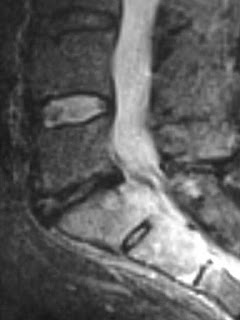

Sagittal T1, T2 and STIR, and axial T1 and T2